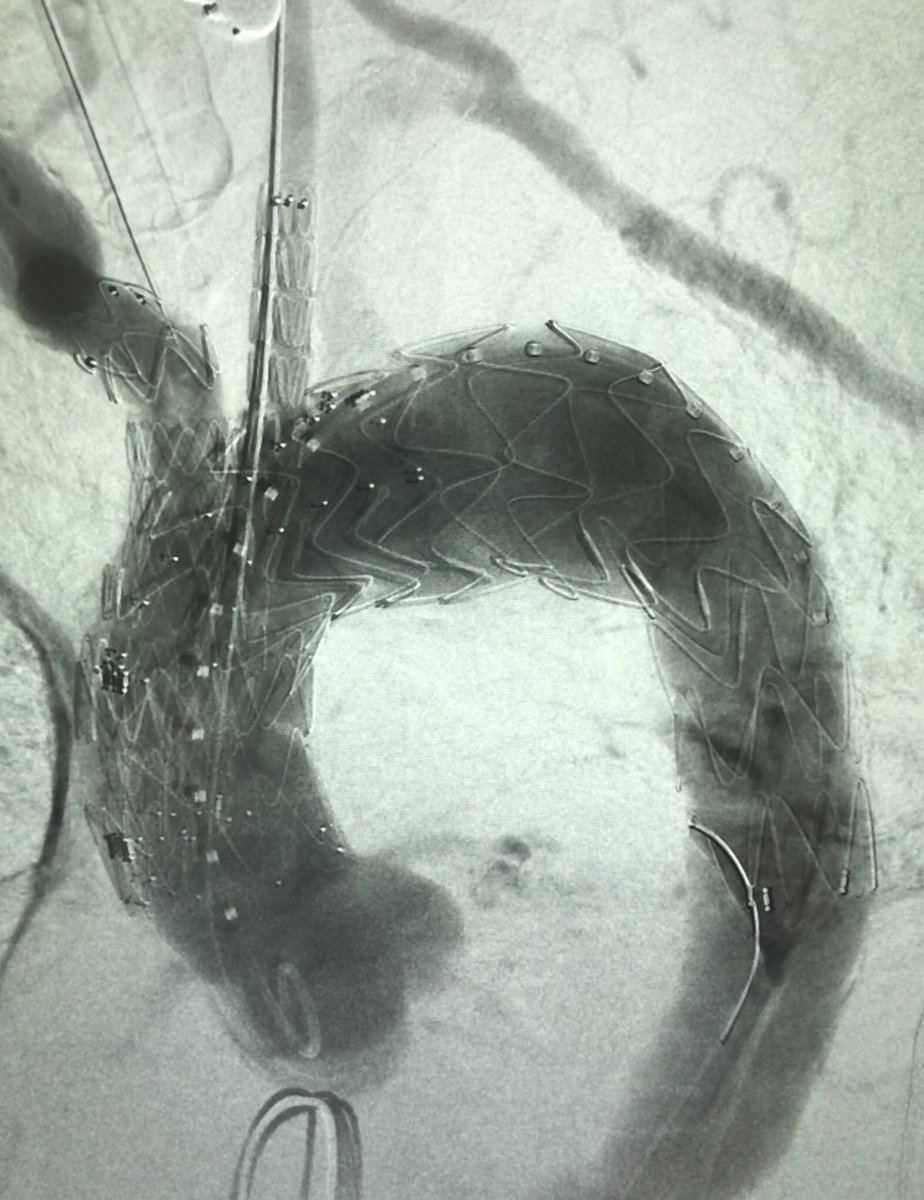

@Parodifeparodi

Ezequiel Parodi

8 years

First Terumo Aortic arch branch at the Cleveland Clinic.